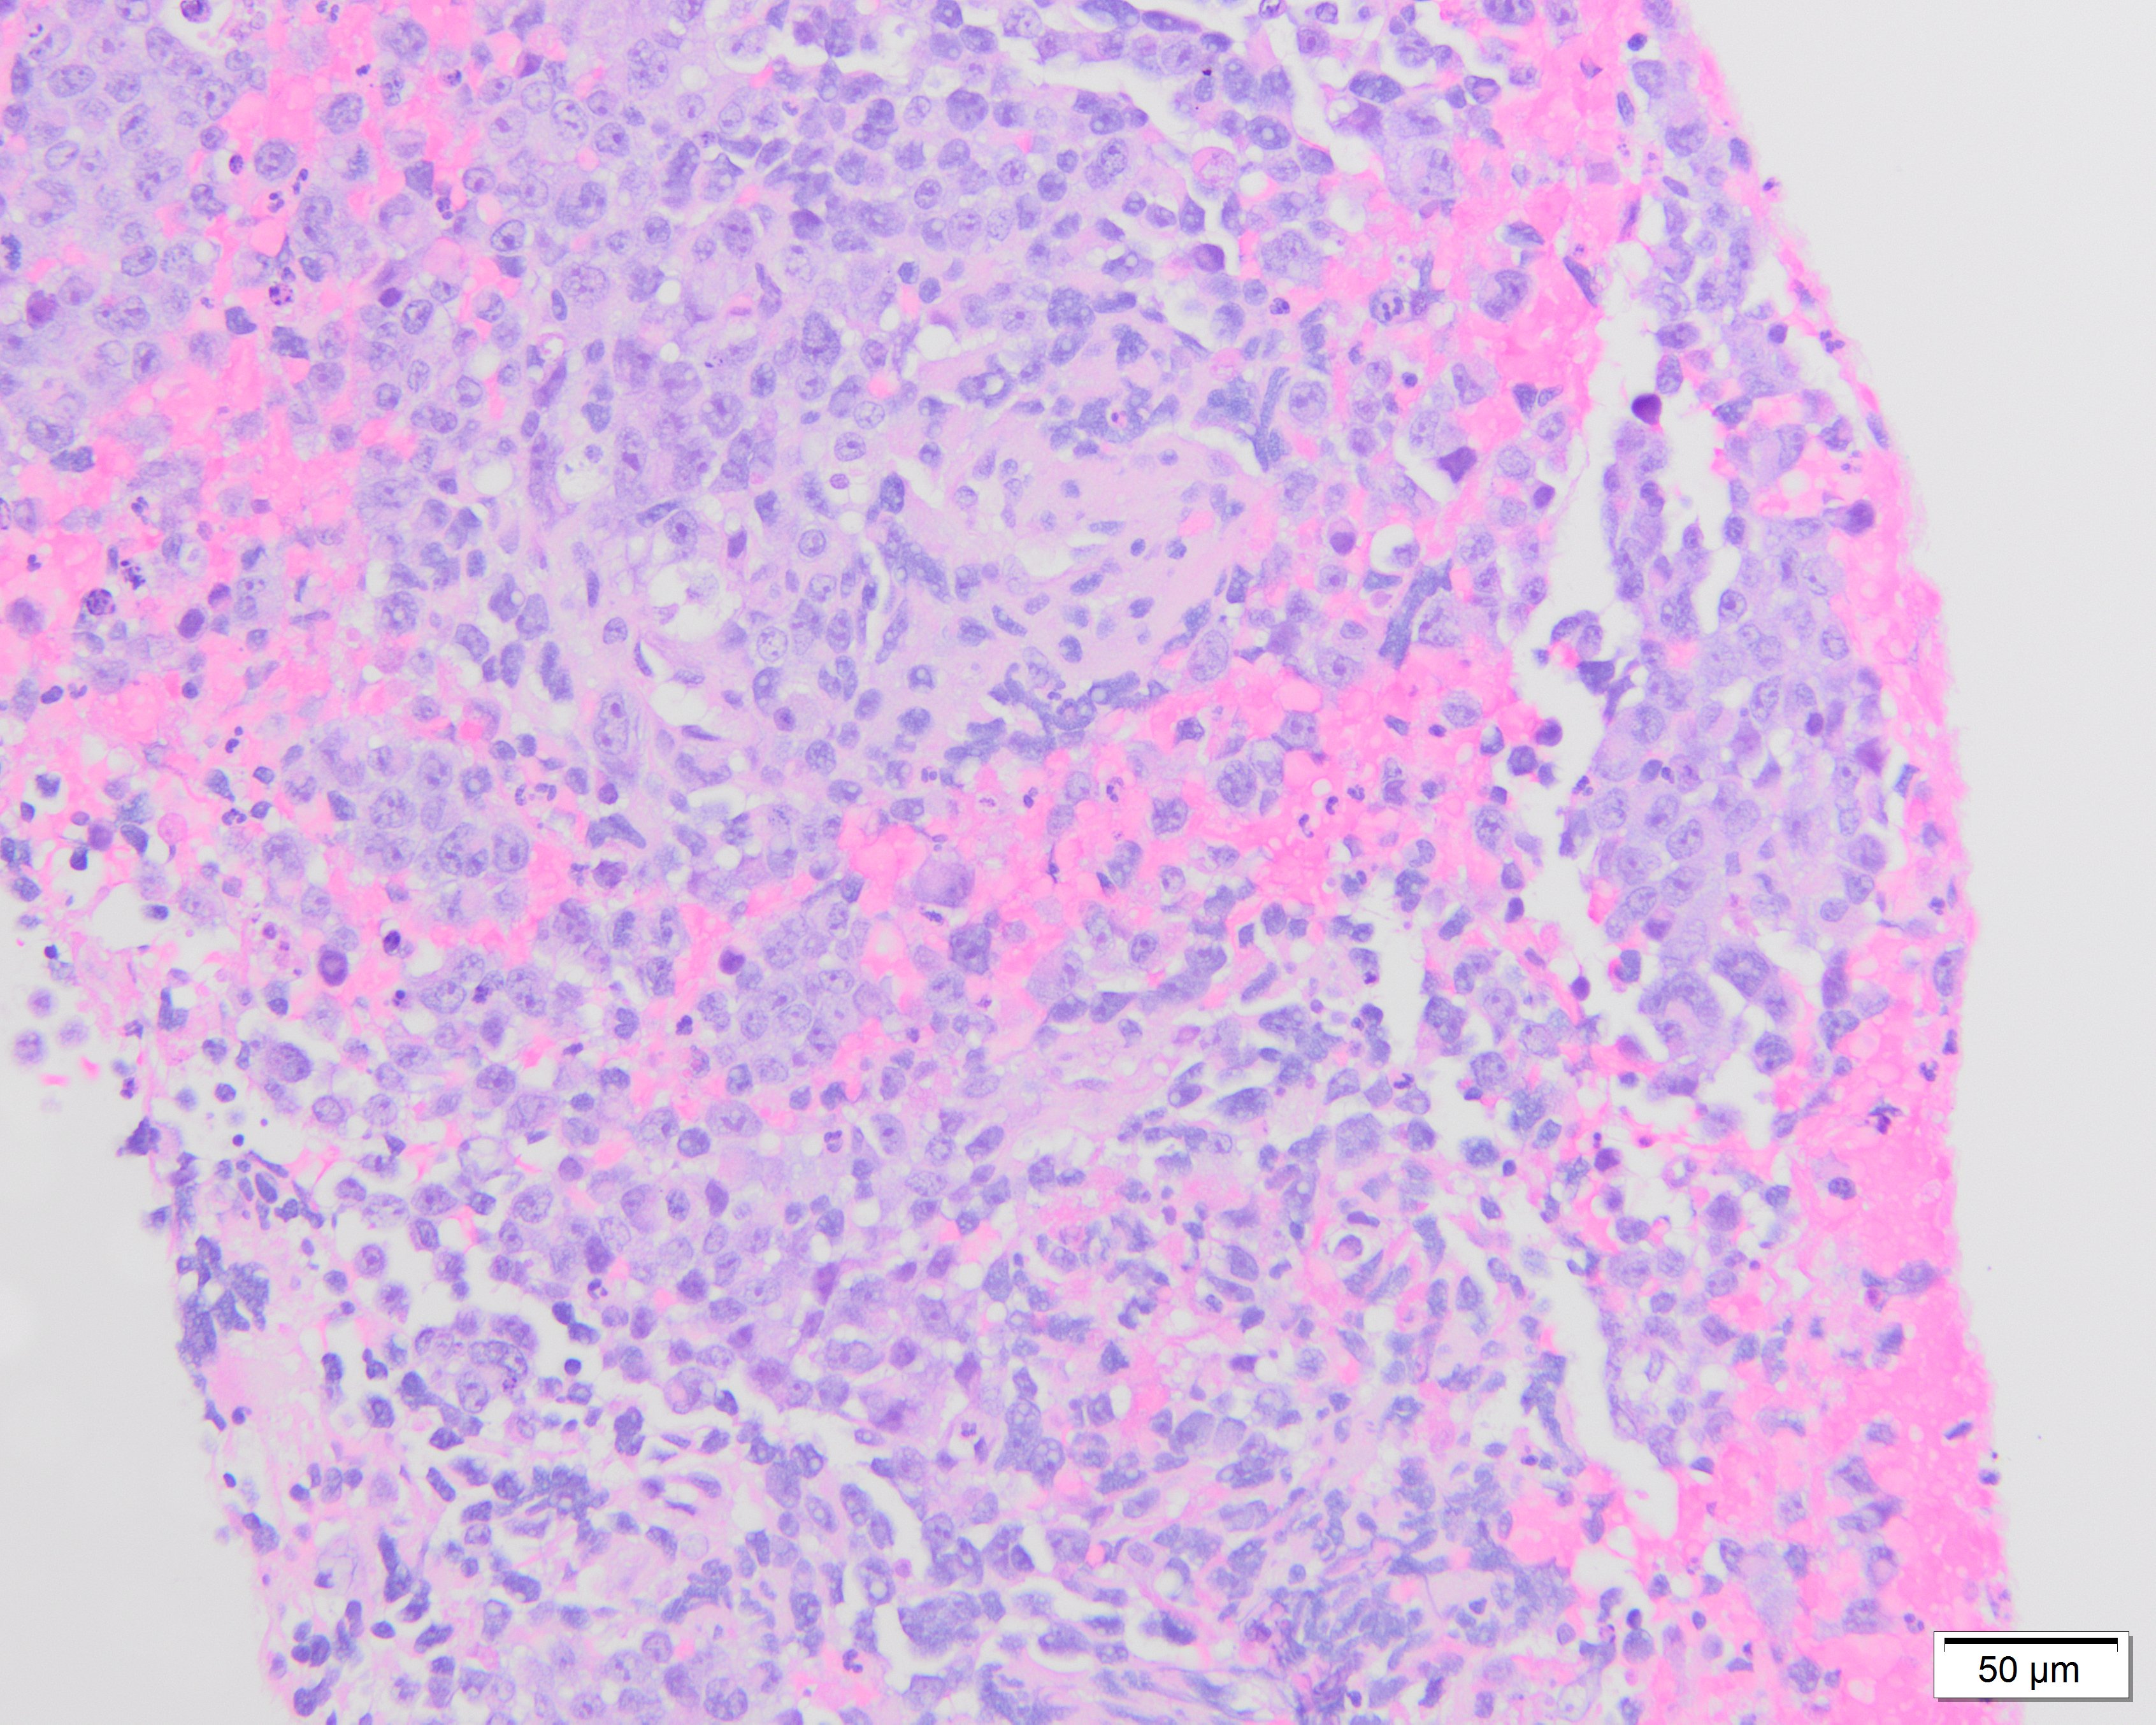

Endobronchial ultrasound (EBUS) biopsy of the station 7/11 left enlarged lymph node was performed and showed undifferentiated epithelioid and pleomorphic round to oval malignant cells.

Tumor cells had prominent nucleoli, with areas of necrosis (Figure 1-2). Immunohistochemical stains showed the tumor cells were focally positive for TTF-1 (Figure 3) and p40 (Figure 4) while negative for CD3 and CD20. NUT immunohistochemical stain was positive in tumor cells in a speckled nuclear pattern (Figure 5).